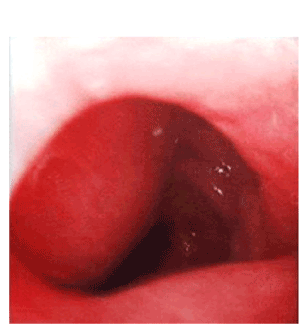

At presentation, his vital signs were stable, and the abdominal examination was unremarkable. The routine blood tests were within the normal range. Gastroscopy showed a deformed duodenal bulb, with narrowing of the 2nd part of duodenum by a smooth convex bulge representing either an external compression or submucosal lesion (Figure 1). Abdominal ultrasound revealed a well-defined (size: 10x6x6 cm) sacculo-tubular mass in the porta hepatis region (Figure 2A). Doppler ultrasound study showed an echogenic thick wall containing a mural thrombus with turbulent arterial flow (Figures 2B). Computed tomography (CT) scan showed a large well-defined hypodense mass with relatively hyperdense periphery arising from the hepatic artery and extending caudally (Figures 2C). A 3D CT-Angiography reconstructed images showed the presence of a huge aneurysm arising from the right hepatic artery (Figure 2D).

Upper GI endoscopy showing the large convex bulge projecting at the inferior wall of second part of duodenum; the mass did not exhibit visible pulsation.